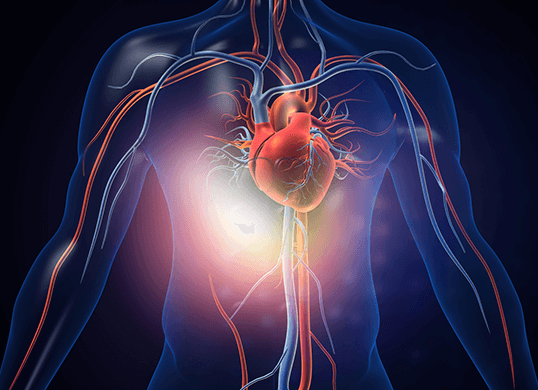

Advanced Heart and Vascular Institute

Advanced Heart and Vascular Institute treats patients with heart disease, venous and varicose vein disease, peripheral arterial disease, and congestive heart failure.

ABOUT US

Advanced Heart and Vascular Institute focuses on minimally invasive surgical and medical treatment of heart, vascular, and venous diseases. We specialize in complex invasive heart and vascular procedures, including coronary artery stenting, lower extremity arterial stenting, and TAVR (aortic valve replacement) without open heart surgery. We also specialize in minimally invasive treatment for varicose vein disease.

The specialists at Advanced Heart and Vascular Institute are high-volume cardiac procedural operators. In fact, they are in the top 5% for volume. This means we have a tremendous amount of experience, providing patients with better results and fewer complications. We treat our patients like family, which makes our treatments and quality of care exceptional.